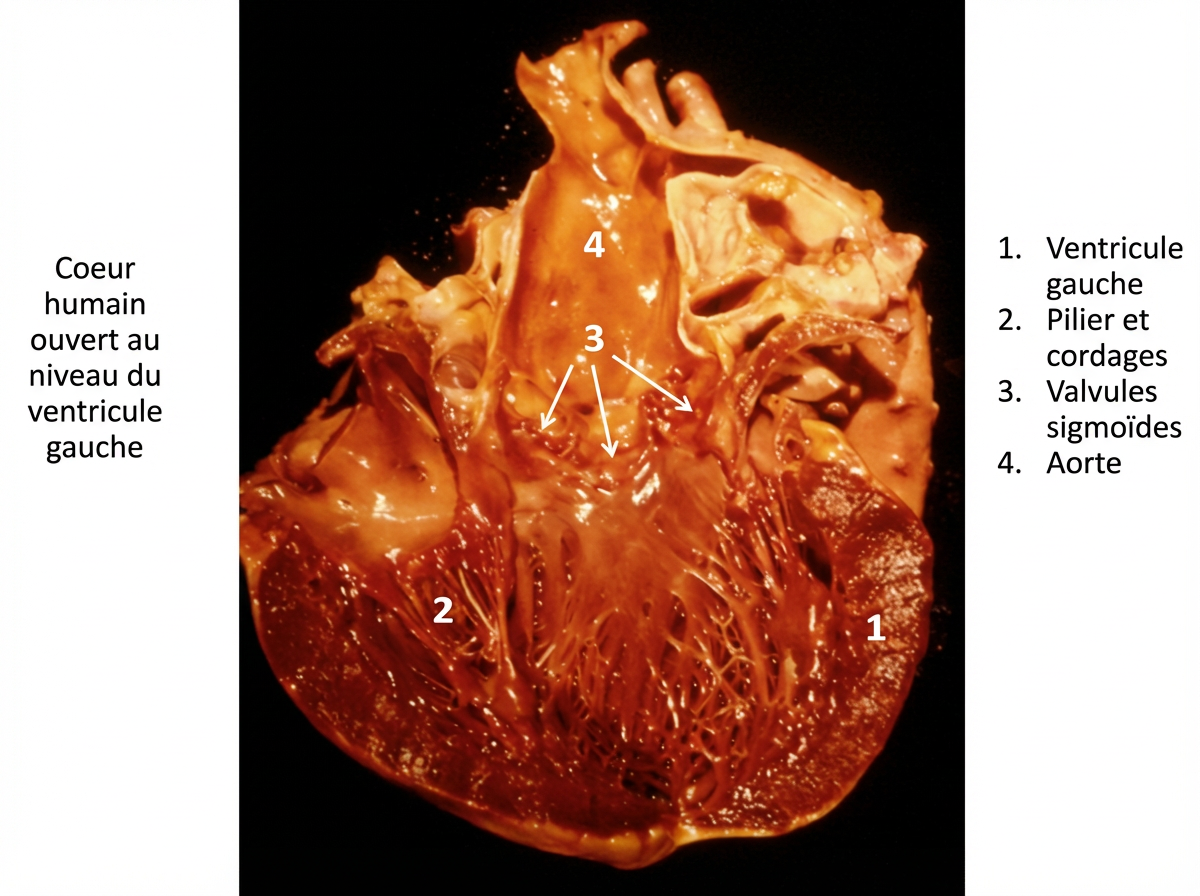

En même temps le travail du cœur est considérable : 3 tonnes de sang sont soulevées de 1 mètre chaque jour, ce qui donne des milliards de pulsations tout au long d’une vie. Les trois valvules sigmoïdes implantées au départ de l’aorte sont conçues pour ne laisser passer le flux que dans un sens. Comme le conduit est cylindrique, elles sont munies sur leur bord libre d’un nodule fibro-cartilagineux de forme triangulaire, si bien qu’aucun reflux de sang ne se produit en position d’occlusion. Sur les veines, des valvules régulièrement espacées suivant la loi de Bardeleben, font progresser le sang d’une manière si bien réglée que ce mécanisme constitue à lui seul une preuve de l’Intelligence créatrice.

Le cœur est un corps de pompe, aspirante[3] et foulante, « à quatre cylindres fonctionnant deux à deux » (Pr Brisssaud), cylindres à mouvements synchrones, avec soupapes et clapets parfaits (valvules), retenus et tendus par de fins piliers, des cordelettes fibreuses, comme des ficelles qui sous-tendent un parachute déployé. Ces piliers du cœur, avec leurs nombreux cordages tendineux sous-tendant les membranes obturatrices délicatement découpées en demi-cercles ou en triangles flottants, sont, à eux seuls d’une formation inexplicable sans Dieu.

On a calculé que la pompe cardio-vasculaire soulevait en moyenne 3.000 kilogrammes par jour à la hauteur d’un mètre. Outre les soupapes, dites valvules, qui séparent les cavités cardiaques, nous devons signaler les valvules placées à la sortie même du cœur, qui sont particulièrement remarquables.

A l’entrée de l’artère aorte existent les valvules, dites sigmoïdes, en nid de pigeon qui, à trois, juxtaposées, laissent bien, en s’affaissant, passer le sang projeté par la pompe cardiaque, mais s’opposent absolument à son reflux.

Mais il y a mieux. Les trois nids de pigeon juxtaposés, accrochés à la même hauteur sur la paroi intérieure du tube, se regardent et se touchent par leur bord libre. Comme ces bords sont arrondis, ils laisseraient, malgré tout, entre eux trois, un petit trou central par où le sang refluerait en partie. Mais une précaution admirable est prise pour obturer d’une façon parfaite le petit espace central qui échappe à l’action des valvules. Il existe au milieu du bord courbe de chacun des trois nids de pigeon une petite pièce fibro-cartilagineuse et calcaire, de forme triangulaire, à arête vive, géométrique, comme on n’en trouve pas ailleurs dans l’organisme (nodule d’Arantius[4].).

Ces trois fibro-cartilages, par leur juxtaposition absolument exacte, ferment hermétiquement et ne laissent pas la plus petite fuite par laquelle puisse refluer le sang dans le cœur gauche.